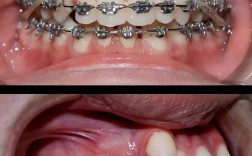

- 传统固定矫正:通过金属托槽、陶瓷托槽与弓丝固定牙齿,适用于各类错颌畸形,尤其是牙齿拥挤、复杂咬合问题,优点是力度稳定、适用范围广;缺点是美观度稍差,口腔清洁难度增加。

- 口腔卫生维护:戴矫正器后食物易嵌塞,需使用正畸专用牙刷(如U型刷、正畸牙刷)、牙线、冲牙器清洁,避免托槽周围龋坏。